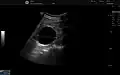

A renal cyst is a fluid collection in or on the kidney. There are several types based on the Bosniak classification. The majority are benign, simple cysts that can be monitored and not intervened upon. However, some are cancerous or are suspicious for cancer and are commonly removed in a surgical procedure called nephrectomy.

Numerous renal cysts are seen in the cystic kidney diseases, which include polycystic kidney disease and medullary sponge kidney.